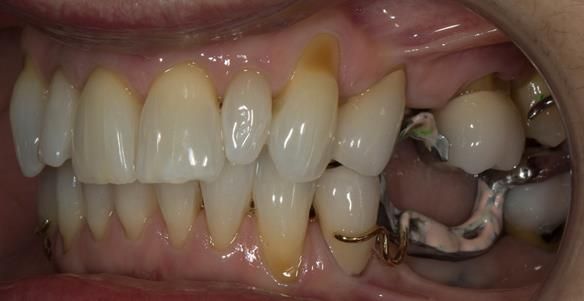

This newsletter describes in step by step detail Angela's transition through immediate partial dentures to crown supported definitive metal based dentures.

The clinical situation and treatment process is shown in detail below with photographs. I (Finlay Sutton) provided the clinical work and Rowan Garstang provided the technical work.